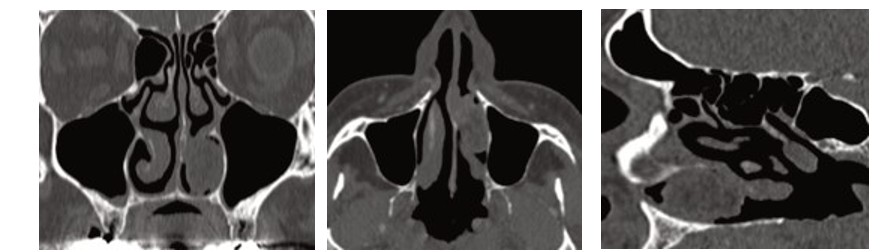

По данным КТ ОНП с в/в контрастированием в просвете нижнего носового хода слева (между медиальной костной стенкой верхнечелюстной пазухи и носовой перегородкой, сверху ограничена нижней носовой раковиной) определяется объемное образование неоднородной структуры с преобладанием жировой компоненты, обтурирует просвет, размеры: аксиальные 25,1˟11,4 мм, коронарный 22,5мм. При контрастировании отмечается неоднородное накопление контраста до +130 едН (преимущественно по контуру и в передних отделах), жировая компонента накапливает до +4 едН. В отсроченную фазу отмечается частичное вымывание контраста. Пневматизация ОНП не изменена, отмечается незначительное утолщение слизистой по нижней стенке правой верхнечелюстной пазухи толщиной до 3мм. Носовая перегородка выраженно отклонена влево на уровне среднего носового хода, в том числе за счет костного шипа до 7-8мм (рис. 1: а,б,в).

Рис. 1. Компьютерная томография ОНП (а - фронтальная проекция; б - аксиальная проекция; в – сагиттальная проекция). Fig. 1. Computed tomography of the paranasal sinuses (a frontal projection; b axial projection; c sagittal projection).